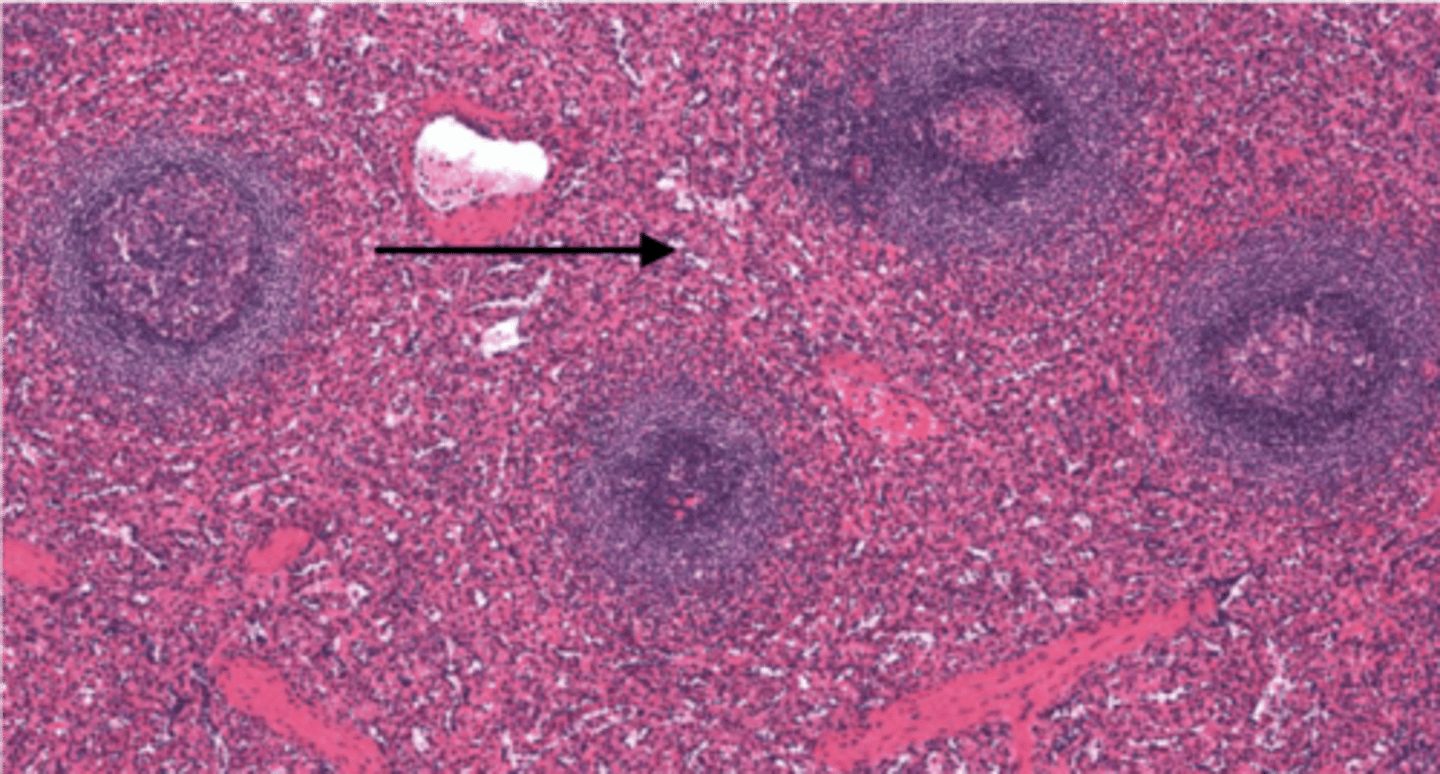

spleen

-the major function of this organ is to scrutinize the incoming blood for aged and malformed erythrocytes

-Will remove RBC and recycle their iron and begin disposal of bilirubin.

-On the lookout for any pathogens organisms or toxic materials in the blood.

red pulp (spleen)

-is the dark red tissue in the spleen containing sinusoidal capillaries, connective tissue fibers, and immune cells like macrophages, plasma cells, and lymphocytes.

-It destroys old red blood cells, removes pathogens and toxins

-facilitates lymphocyte movement between splenic tissue and blood.

white pulp (spleen)

has whitish appearance in a fresh spleen. Lymphocytes, macrophages surrounding small branches of splenic artery